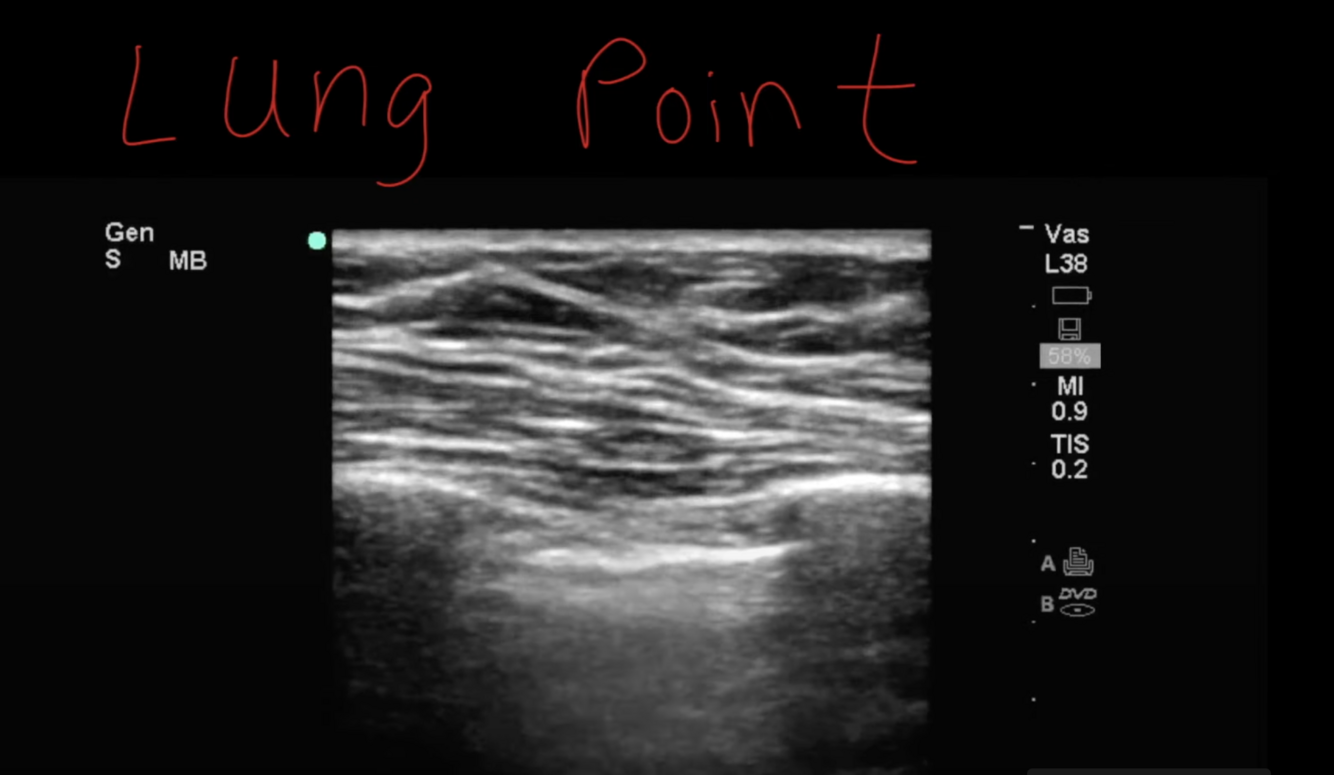

Ultrasonography allows visualization of the parietal and visceral pleura; inability to detect lung sliding, the 2 pleural layers moving against one another during respiration, is consistent with pneumothorax. Visualization of sliding is enough to out pneumothorax (99-100% negative predictive value). The inability to see lung sliding is not sufficient to rule in pneumothorax (lack of sliding could be from an emphysematous bleb, pleurodesis, or infection from pneumonia). To rule in pneumothorax on ultrasound, what is required is visualization of the lung point, the boundary between air and the visceral pleura (with the exception being a complete pneumothorax).